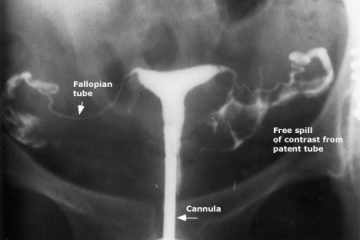

Các phương pháp chuẩn đoán vô sinh – hiếm muộn cho nữ giới

Chúng ta có rất nhiều cách để chẩn đoán vô sinh – hiếm muộn ở nữ giới nhờ những tiến bộ của y học hiện nay. Tùy vào tình trạng của ...